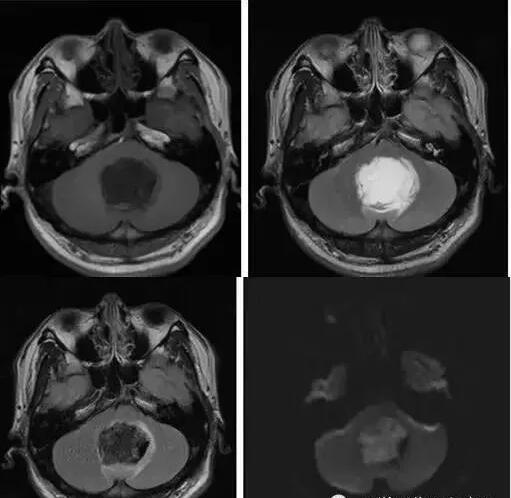

MR表現(xiàn):

①鞍上池或橋小腦角池類圓形或不規(guī)則病變,邊緣銳利。

②T1加權(quán)絕大部分為均勻的低信號,少數(shù)由于瘤體內(nèi)含液態(tài)膽固醇或出血而呈高信號影。T2加權(quán)呈明顯的、均勻一致的高信號影,高于腦脊液信號;DWI可見高信號。

③腫瘤包膜于T1加權(quán)呈中等信號,T2加權(quán)呈高信號影。

④增強檢查無強化效應(yīng)。